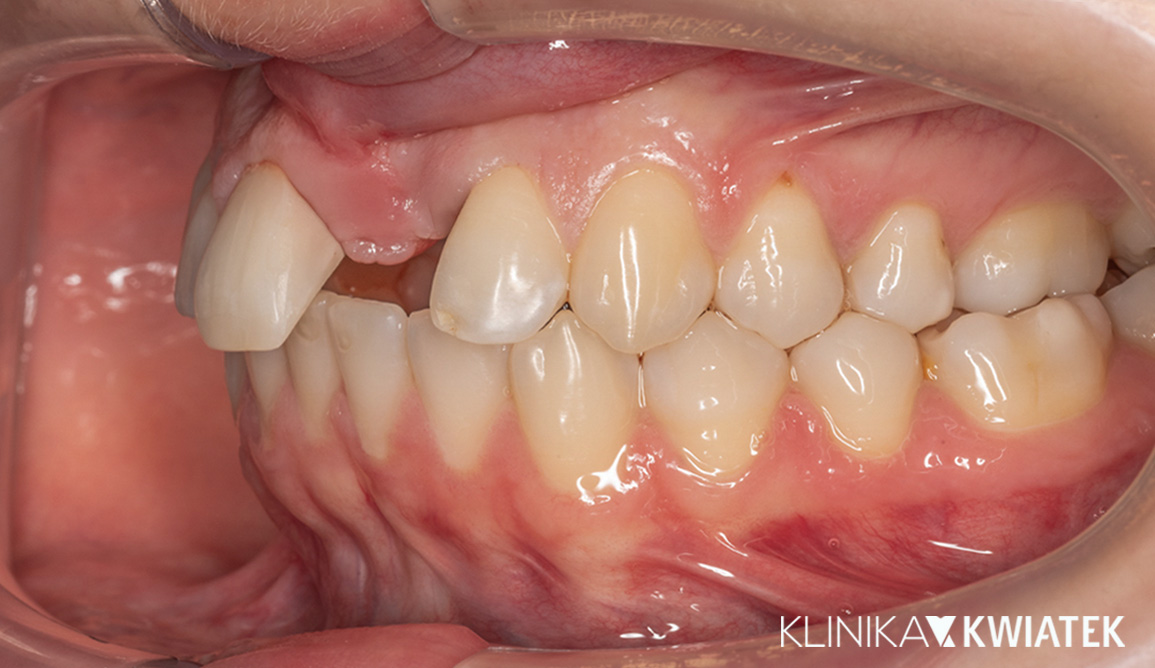

Pacjentka zgłosiła się z wadą zgryzu, licznymi ubytkami i utraconymi zębami trzonowymi, co powodowało trudności w żuciu i estetyczne niezadowolenie. Leczenie obejmowało ekstrakcje, ortodoncję, implantację oraz kompleksową rekonstrukcję protetyczną. Po kilkunastu miesiącach terapii Pacjentka odzyskała pełną funkcję zgryzu i piękny, harmonijny uśmiech.